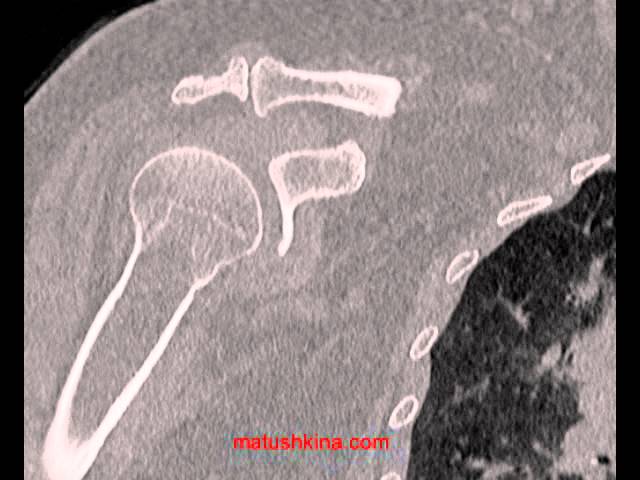

Компьютерная томография плечевого сустава является диагностической процедурой. Никакого лечебного воздействия не оказывает. Отличается высокой информативностью и безболезненностью, позволяет определить наличие патологий и изменений в суставе, которые не видны при других способах исследования.

В основе процедуры лежит использование рентгеновских лучей низкой интенсивности. Обработка организма выполняется тонкими пучками лучей, которые захватывают тонкий слой ткани (толщиной от 0,5 до 10 мм). Для получения полноценной картины выполняется несколько последовательных излучений, при каждом последующем просвечивается следующий участок тканей, причем предыдущий полностью изолируется от лучей. Благодаря этому томография позволяет достичь нескольких целей одновременно:

КТ и МСКТ плечевого сустава в качестве результата предоставляют снимки, которые впоследствии врач описывает. Их и получает пациент на руки после обследования. На основании полученных результатов врач может дать направление к узкому специалисту.

Показывает компьютерная томография следующие возможные отклонения:

- Высокое качество изображения, при желании разрешение можно увеличить еще больше.

- Высокая информативность при изучении аномалий костей и суставов. Если сравнивать с УЗИ, то это преимущество, поскольку ультразвук в твердые ткани не проникает, а значит, и никакой информации о них не дает.